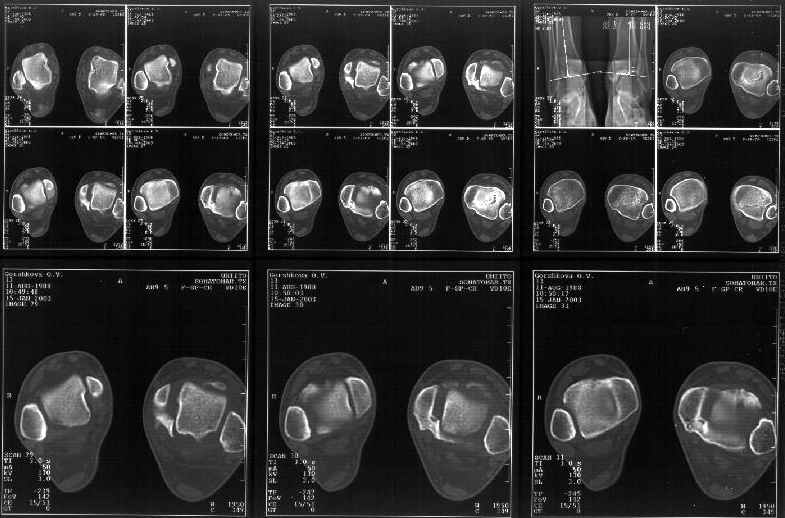

Мне в тоже время совершенно ясно видно по той же КТ, по 4 срезам, расположенным в центре и вверху пленки, что перелома внутренней лодыжки не было, в следующем собщении я приложу увеличенный фрагмент томограммы. А к этому письму прилагаю увеличеный фрагмент послеоперационной рентгенограммы, где выделил отколотый фрагмент

позади внутренней лодыжки. И он, как я вижу, находится между стержнем и тараном. А перелома внутренней лодыжки, и тем более смещения, IMHO

не определяется.

Здесь 4 среза, начиная от основания лодыжки и проксимальнее. Где, по Вашему мнению, проходит линия перелома, отделяющая переднюю часть внутренней лодыжки от большеберцовой кости? Заранее спасибо.

Я пометил линию перелома черной линией.

К сожалению на последних присланных срезах КТ нет более низкого, через таран, среза, который был на прежнем майле. На XR я попытался показать

стержень внутри сустава и то как он раскрывает пространство между тараном и мед. малеолом.

Сегодня пациентке сделали сравнительную КТ. А ксиальные и Фронтальные срезы приложены. Ваше мнение?

Фронтальные

Аксиальные